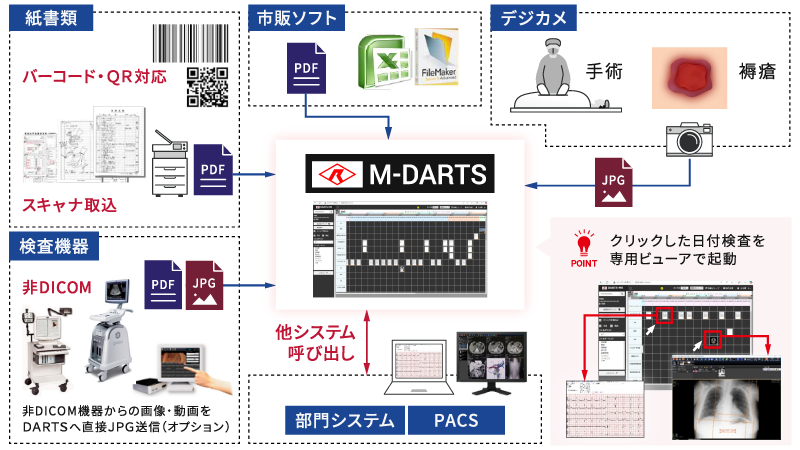

DICOM/非DICOMデータを一元管理

DICOM/非DICOMデータを一元管理

DICOMだけでなく、非DICOMデータや他の標準フォーマットもサポート。

異なるPACSやEMRシステムとシームレスに連携できる機能で、互換性を最大限確保します。

■統合Viewer M-DARTS

DICOMキー画像をはじめ、スキャン画像データやデジカメ画像データ等の非DICOM画像を一元管理・表示する統合Viewerです。

システム概要図